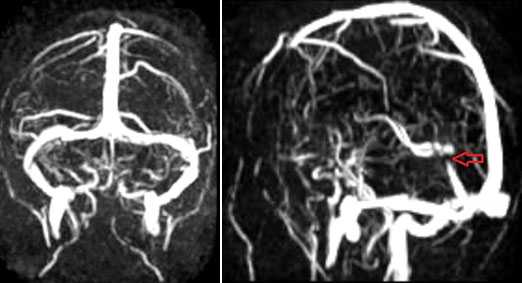

СТЕНОЗЫ, УЧАСТКИ ПАТОЛОГИЧЕСКОГО РАСШИРЕНИЯ И ГИПОПЛАЗИЯ ВЕНОЗНЫХ СТРУКТУР ГОЛОВНОГО МОЗГА

МРА-картина выраженной асимметрии венозной сети с преобладанием и нерезкой дилатацией вен правой гемисферы (поперечного, сигмовидного синусов и яремной вены справа); гипоплазии левого поперечного и сигмовидного синуса. Единичные участки (2) локального расширения вен в парасагиттальных отделах левой гемисферы, большой вены мозга. Асимметричная, расширенная и выражено извитая венозная структура экстракраниальных отделов справа.

МРА признаки незначительной дилатации верхнего сагиттального синуса, локального снижения кровотока и сужения просвета дистальных отделов прямого синуса; асимметрии просвета поперечных, сигмовидных синусов и внутренних яремных вен.